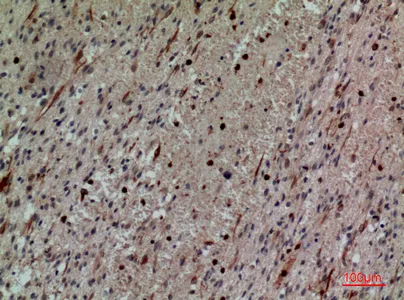

CD13 Rabbit Polyclonal Antibody

Cat: APRab08201

Size1:50μl Price1:$118

Size2:100μl Price2:$220

Size3:500μl Price3:$980

Size2:100μl Price2:$220

Size3:500μl Price3:$980